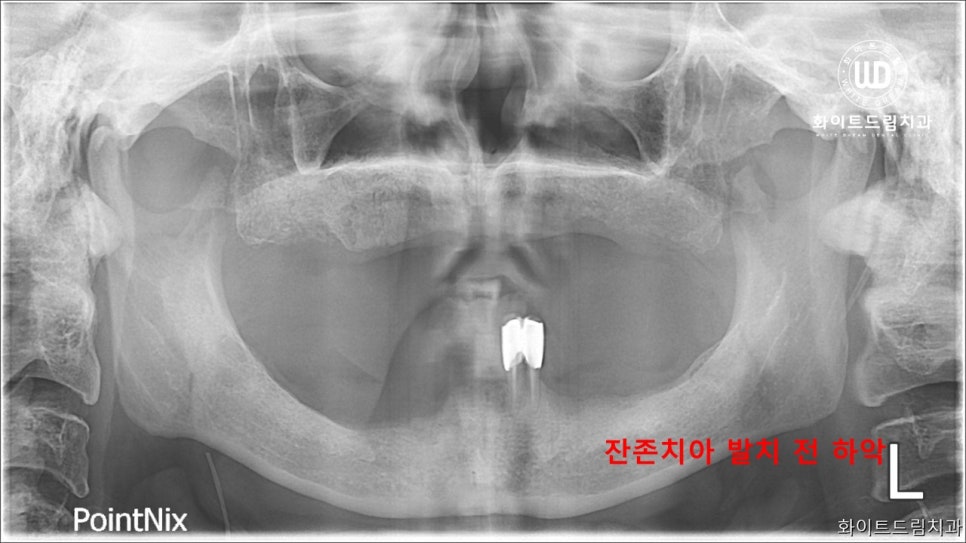

더욱 자세한 치료를 위해 파노라마 사진을 촬영하여 살펴보았습니다. 하악의 잔존 치아도 제 기능을 하지 못할뿐더러 골소실이 함께 나타나 있었습니다. 그래서 하악 잔존 치아 2개를 발치하여 상하 전체 치조골 이식을 동반한 임플란트 식립을 진행하였습니다.

임플란트 치료를 받고자 하는 많은 환자분들께서 뼈가 부족한 상태로 내원하는 경우가 많습니다. 잇몸 뼈의 조건이 좋지 못하면 임플란트 보철을 식립하기 어려울 수 있는데요. 특히나 까다로운 경우가 전치부쪽입니다.

어금니쪽은 잇몸면적이 그나마 넓은 편에 속하지만, 전치부는 잇몸뼈가 얇아지기 때문에 식립이 상당히 까다로운 편에 속합니다. 현재 전악케이스인 환자분의 경우에는 앞니뿐만 아니라 오랜시간 틀니를 착용하면서 어금니쪽 잇몸뼈도 그리 좋은 상태가 아님을 확인할 수 있습니다.